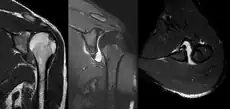

A diagnosis of shoulder dislocation is often suspected based on the person's history and physical examination. Radiographs are made to confirm the diagnosis. Most dislocations are apparent on radiographs showing incongruence of the glenohumeral joint. Posterior dislocations may be hard to detect on standard AP radiographs, but are more readily detected on other views. After reduction, radiographs are usually repeated to confirm successful reduction and to detect bone damage. After repeated shoulder dislocations, an MRI scan may be used to assess soft tissue damage. In regards to recurrent dislocations, the apprehension test (anterior instability) and sulcus sign (inferior instability) are useful methods for determining predisposition to future dislocation.

A Hill–Sachs lesion is an impaction of the head of the humerus left by the glenoid rim during dislocation.[6] Hill-Sachs deformities occur in 35–40% of anterior dislocations. They can be seen on a front-facing X-ray when the arm is in internal rotation.[11] Bankart lesions are disruptions of the glenoid labrum with or without an avulsion of bone fragment.[12]

- An anterior dislocation of the shoulder

Anterior dislocation of the right shoulder. AP X ray

Anterior dislocation of the right shoulder. Y view X ray.